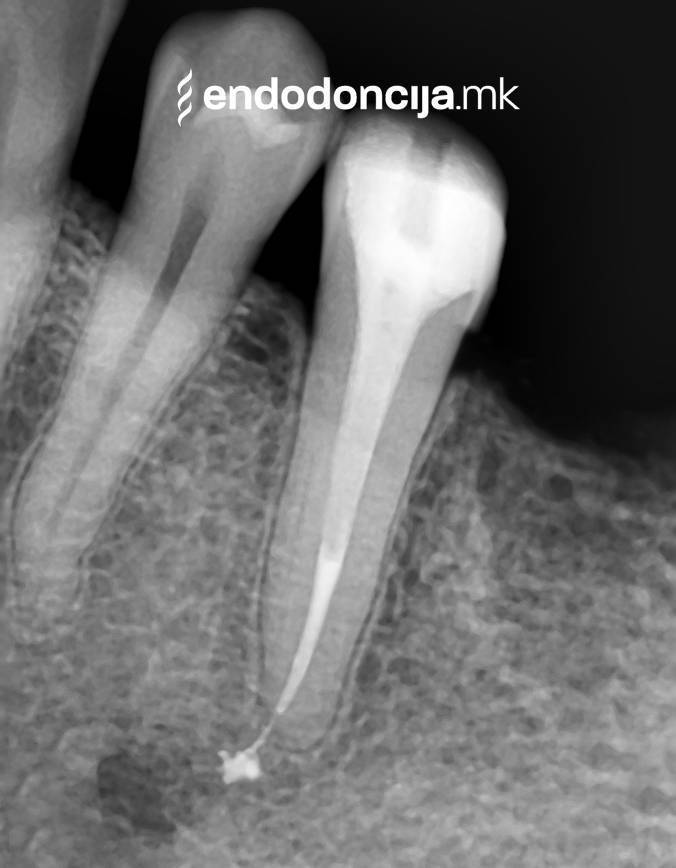

Σε περίπτωση ανανέωσης της θεραπείας του ριζικού καναλιού (αναθεώρηση) παλιά γεμίσματα ρίζας που δεν ήταν επιτυχημένα και ως εκ τούτου ήταν η αιτία φλεγμονών και πόνου, μπορούν να αφαιρεθούν και να ανανεωθούν εξειδικευμένα. Αυτή η θεραπεία εξαλείφει τις φλεγμονές στην περιοχή της ρίζας και καθίσταται δυνατή η πλήρης ανάρρωση.

Εκτός από την ανίχνευση των ριζικών καναλιών, η ενδελεχής προετοιμασία και η απολύμανση του ριζικού σωλήνα είναι η προϋπόθεση για μια επιτυχημένη συνολική θεραπεία. Μέσω της χρήσης των νεότερων οργάνων και αντιβακτηριακών διαλυμάτων, όλα τα υπολείμματα ιστών και τα βακτήρια που υπάρχουν μπορούν να εξαλειφθούν.

Με τη σωστή θεραπεία, όχι μόνο οι οξείες φλεγμονές αλλά και οι χρόνιες μπορούν επίσης να αντιμετωπιστούν με επιτυχία. Αυτά μπορεί να προκαλέσουν πόνο ή μερικές φορές ακόμη και εντελώς χωρίς συμπτώματα. Η έγκαιρη ανίχνευση και εξάλειψη τέτοιων φλεγμονών είναι ζωτικής σημασίας για τη μακροχρόνια συντήρηση των δοντιών.